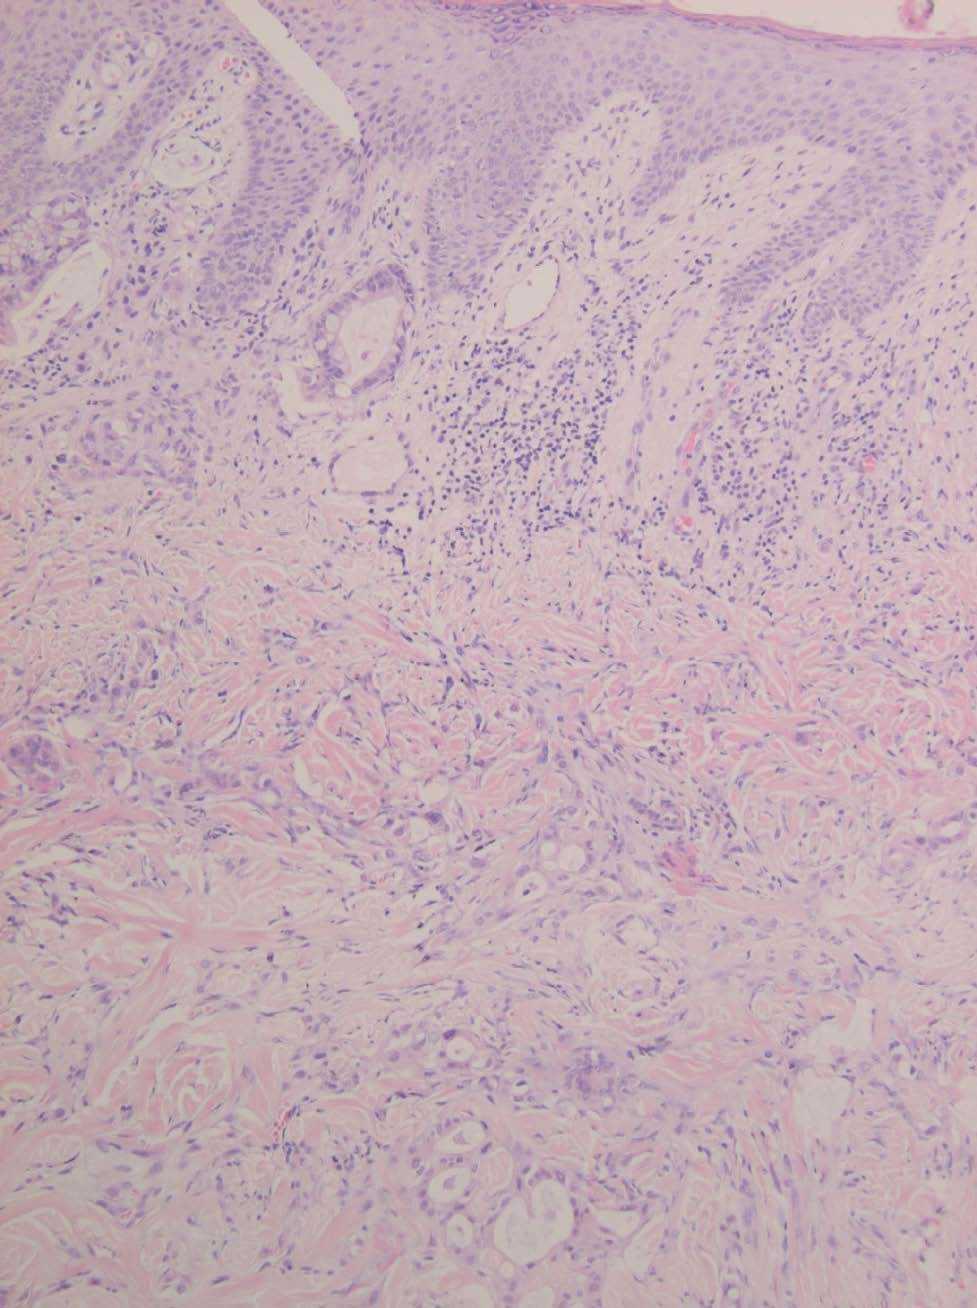

El estudio histológico de una biopsia de la lesión se muestra en las figuras 2 y 3.

Fig. 3.--Detalle histológico. Positividad para antígeno carcinoembrionario (CEA).

El examen histopatológico muestra una dermis con numerosas formaciones glandulares (fig. 2). A mayor aumento se aprecia que las formaciones glandulares están constituidas por células poligonales y cilíndricas con presencia de moco en su interior, con núcleos pleomórficos e hipercromáticos, y con presencia de nucleolos. El estudio inmunohistoquímico demuestra una positividad para el antígeno carcinoembrionario (CEA) (fig. 3) y la citoqueratina (CK) 20, siendo negativa la CK7. El resultado de la biopsia de la neoformación colónica revela la presencia de un adenocarcinoma bien diferenciado, con áreas coloides, infiltrante, sobre adenoma velloso.